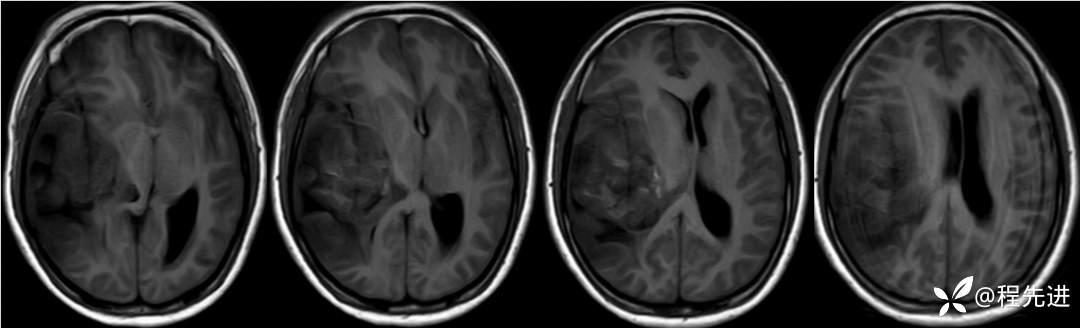

T1: